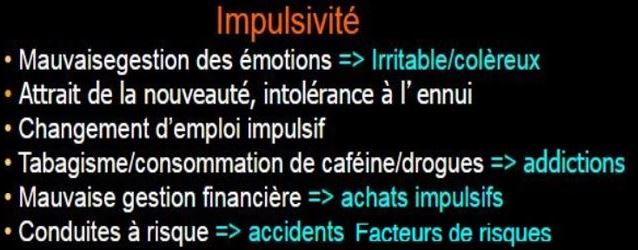

Type impulsifTrès médiatisé chez les enfants durant ces dernières années, les adultes hyperactifs sont devenus avec l’âge moins agité physiquement, mais passent inlassablement d’une action à un autre sans en terminer la plupart, les empêchant d’atteindre leurs objectifs trop nombreux ou incompatibles avec leur trouble.

– Ce sous-type concerne un peu plus les jeunes garçons et les hommes.

– Ne pas confondre avec les hyper-actifs (en 2 mots), qui ont une multitude d’activités, mais qui s’organisent bien et mènent généralement à bout ce qu’ils entreprennent.

Ils agissent ou parlent avant de réfléchir, prennent des risques, ont un tempérament explosif ou simplement plaquent tout régulièrement.

– Cela peut être visible de l’extérieur (plus masculin) ou rester interne, et cela peut induire d’étranges comportements irréguliers, avec une vie interne très mouvementée, alternant les émotions agréables et désagréables très rapidement.

– Ils peuvent avoir tendance à interrompre les autres dans une conversation, à consommer des drogues légales et illégales pour calmer cette impulsivité

| ► Si elle

existe, l’impulsivité peut être visible et audible, souvent liée

à une hyperréactivité aux émotions. – Ils ont « la mèche courte » comme on dit au Québec; en France on dit plutôt « soupe au lait ». – Mais beaucoup peuvent rester calmes extérieurement, telle une cafetière italienne qui ne bouge pas mais dans laquelle le café monte et pour certains quelquefois déborde, soit dans le domaine professionnel soit personnel. ► L’impulsivité peut faire prendre de mauvaises décisions comme quitter prématurément une relation ou un job sur un coup de tête. → Mieux contrôlée elle permet de dynamiser les échanges ou de ne pas s’enliser dans une situation sans avenir, par exemple un job incompatible avec le trouble du déficit de l’attention, c’est-à-dire qui demande beaucoup de rigueur et de régularité sans créativité ni autonomie. – Combiné à la distraction, l’impulsivité est une des causes majeures d’accidents de la route chez les TDAH, plus fréquents que la moyenne des gens dans les statistiques américaines. ► Certains peuvent être très irritables ou colériques, et être ainsi de vrais tyrans avec leurs proches, souvent sans en être vraiment conscients sur le moment. – D’autres ressentent une forte irritabilité quand il y a trop de stimuli ou quand ils se sentent dépassés, comme un orage intérieur qui ne fait que passer mais qui peut déconcerter ou blesser leur entourage. ⇒ On leur dit qu’ils sont bons et méchants en alternance (Docteur Jekyll et M Hyde). – Certains peuvent bloquer cette hyper-émotivité mais répriment leurs émotions qui vont se stocker dans le corps et générer des tensions qui peuvent se transformer un jour en maladies psychosomatiques de toutes sortes. ► Beaucoup piquent souvent une crise de nerf ou « pètent un plomb » comme ils disent, certains se sentent dirigés par un monstre à l’intérieur d’eux. – Consécutivement une culpabilité peut les déprimer pendant quelques jours. – Certains ont la présence d’esprit de se retirer au lieu d’agresser leur entourage. – D’autres sont des agresseurs permanents; ce sont souvent des hommes et ne cherchent pas à se remettre en question et s’améliorer donc ce sont souvent leur épouse qui découvre qu’il s’agit du TDAH. ► Cette impulsivité peut générer dès l’enfance et au fil du temps des troubles importants du comportement : – Des troubles oppositionnels avec ou non provocation (TOP), des comportements négatifs face aux figures d’autorité. – Cela reste souvent une attitude interne négative permanente qui s’oppose à tout ce qui se dit et se passe autour de soi, avec de l’agacement, de la colère, ou des ruminations interne seulement. – Un trouble de l’opposition d’un enfant TDAH peut évoluer à l’âge adulte vers une asociabilité et une solitude extrême. – Des troubles des conduites (TC), comportements agressifs (bagarre, menace, vol, fraude, …) à l’adolescence, qui peuvent évoluer vers une délinquance extrême qui se terminera alors en prison, car le manque d’anticipation et de réflexion ne leur permettra pas d’échapper aux autorités à l’âge adulte. |

|